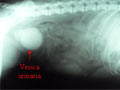

Penanganan Kasus Urolithiasis (Batu Ginjal) pada Anjing

DOGfans News edisi 83/Mei 2008